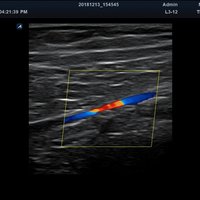

• Vaskulär

Anwendungsbereiche Abdomen MSK, Nerven, Karotis, periphere Gefäße, Schilddrüse, Mamma

Bildgebungs-Modi B-Modus, CF, M, PW, PD B-Modus, CF, M, PW, PD

• Farbdoppler: farbige Darstellung der Richtung des Blutflusses